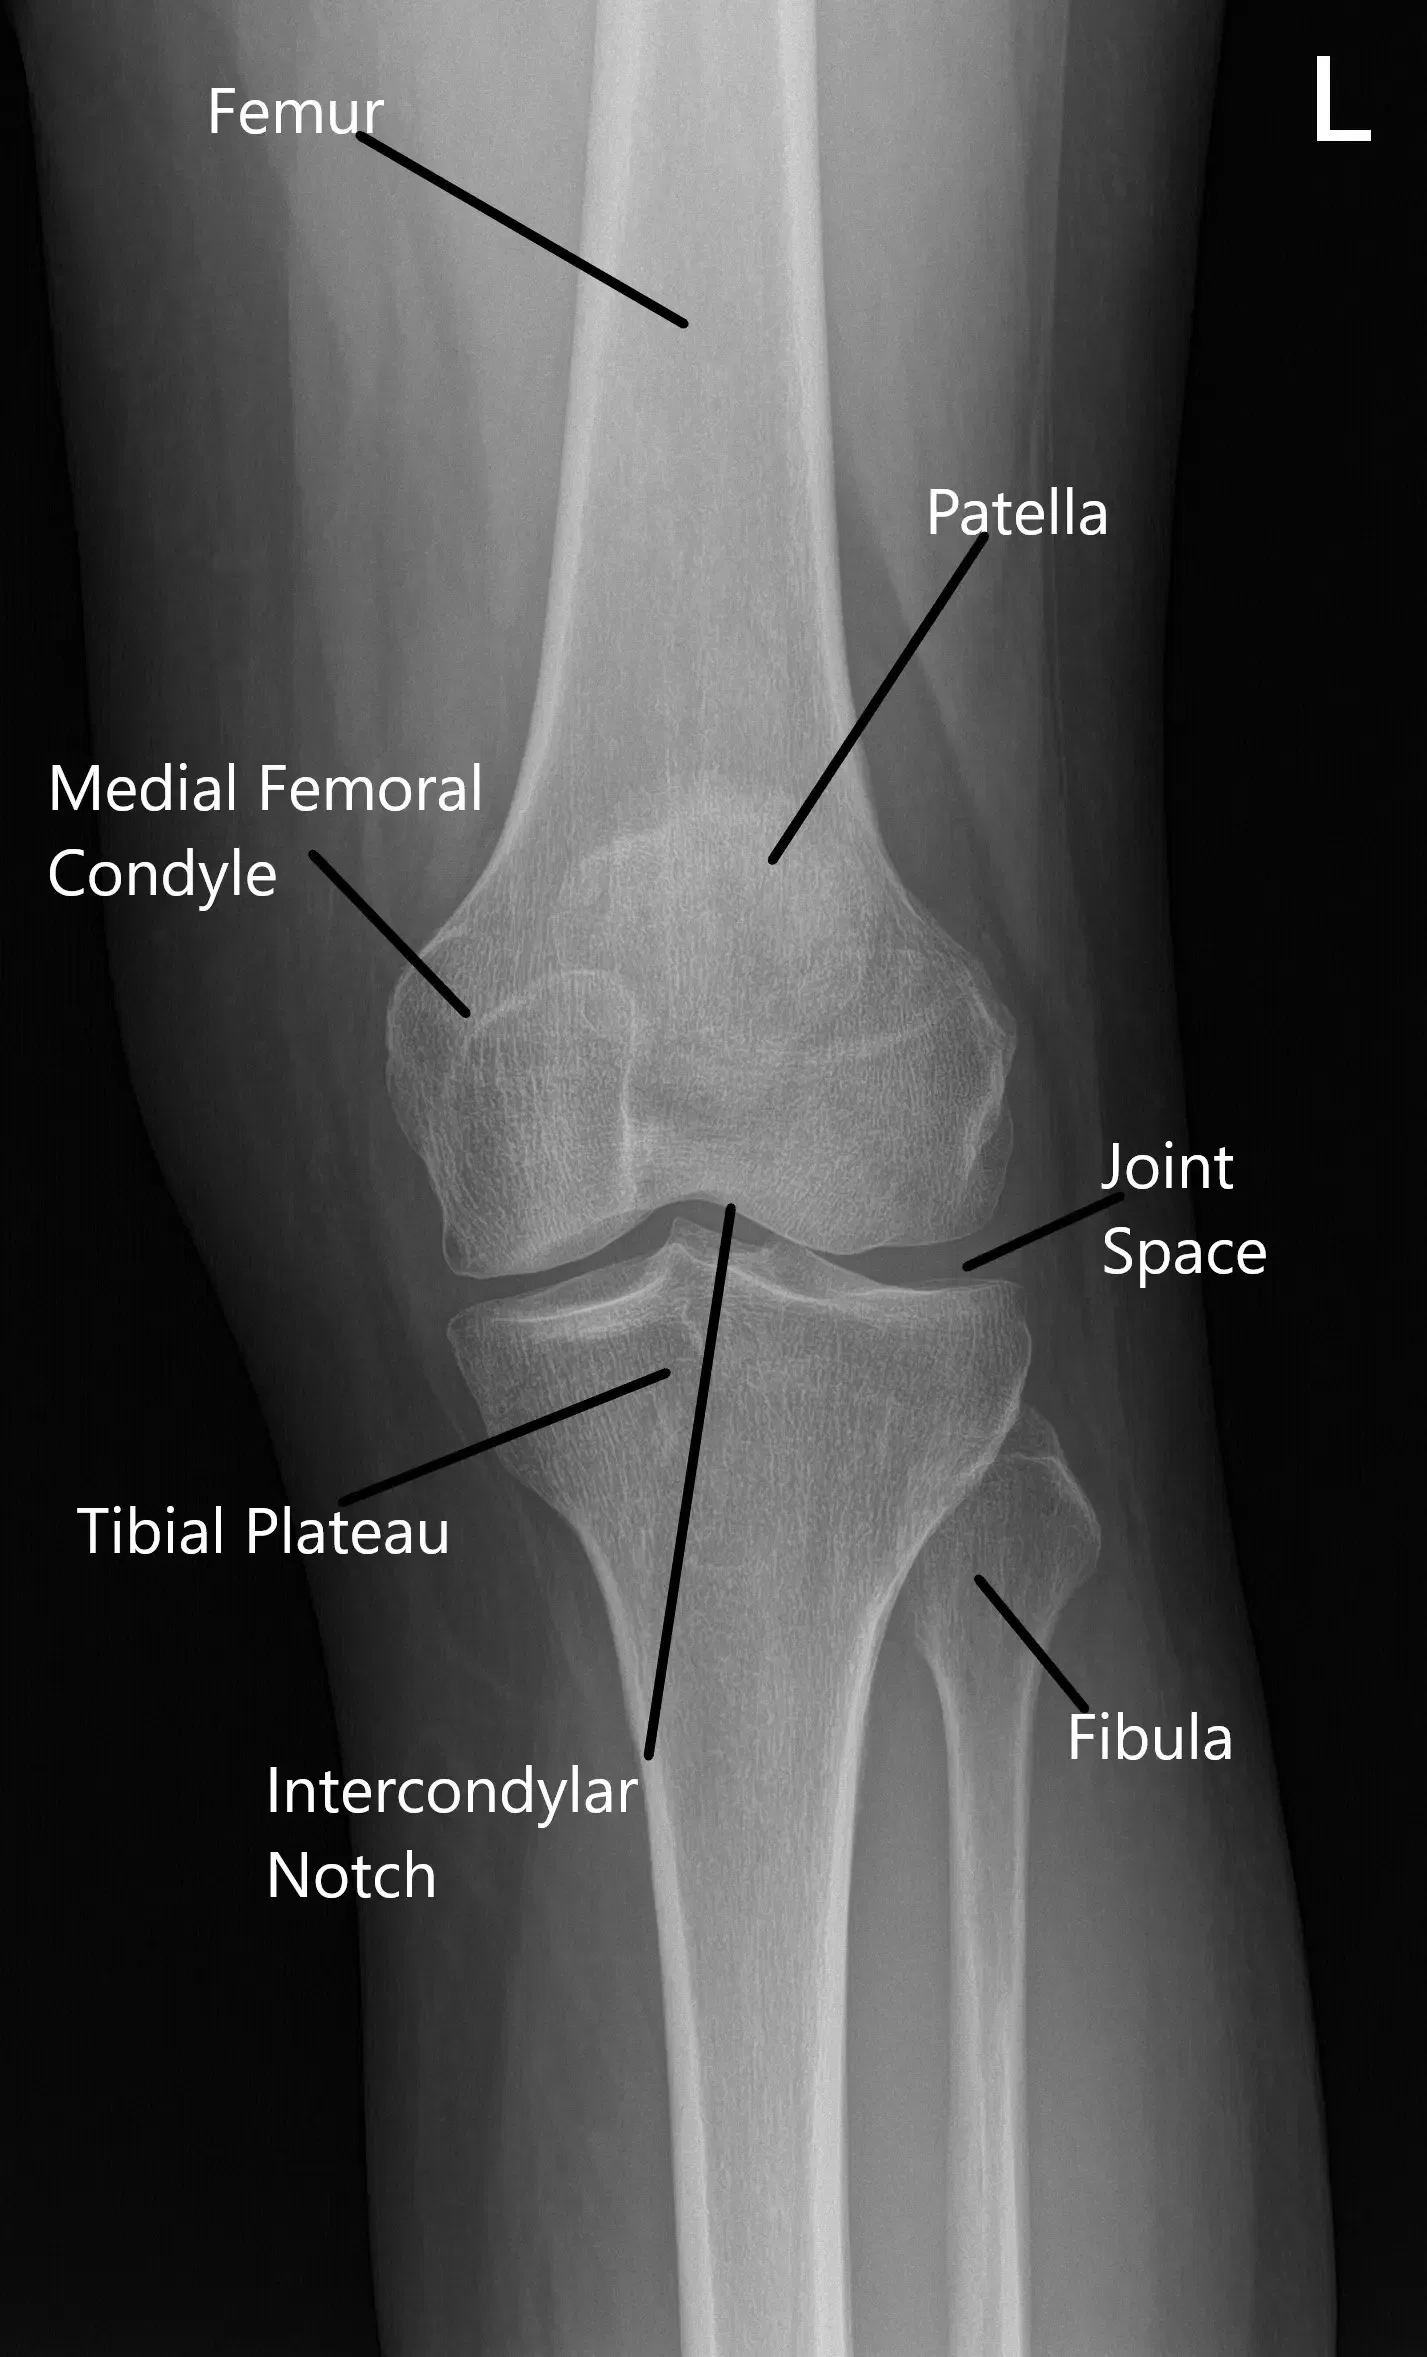

The patellofemoral joint is where the patella (kneecap) rests within the groove of the femur (thigh bone). The knee joint functions by allowing smooth bending and straightening movements, with the patella helping to stabilize and guide these motions. In PFPS, the alignment of the kneecap becomes compromised, often due to muscle imbalances, tight ligaments, or poor training, leading to pain and discomfort.

Normal X-ray of the knee joint showing the various structures in the Anteroposterior and Lateral view.